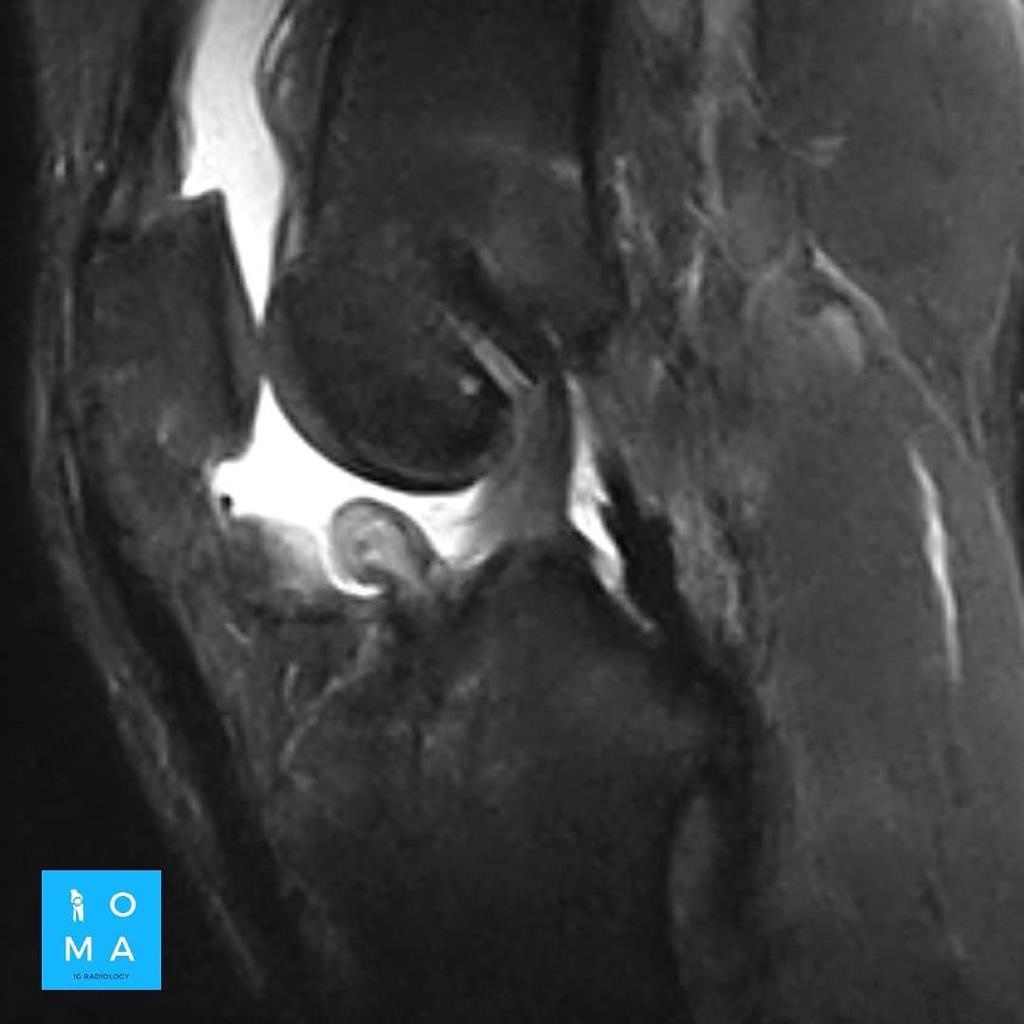

Se presenta caso de paciente de la 3a década, que en su embarazo se diagnostica con sospecha de adenoma y posterior al embarazo se realiza estudio de control contrastado para su mejor diferenciación.

En la evaluación con medio de contraste, se evalúa la relación arterial y de las venas, esto puede servir para buscar la arteria central relacionada con la hiperplasia nodular focal o bien, para evaluar la relación con las estructuras vasculares que son muy importantes para el planeamiento quirúrgico .

en este caso, aún cuando los hallazgos son atípicos tanto para hiperplasia nodular focal como para adenoma, nos inclinamos hacia el diagnóstico de adenoma debido a los antecedentes de la paciente, el tamaño de la lesión, el área de sangrado, el contenido de grasa.